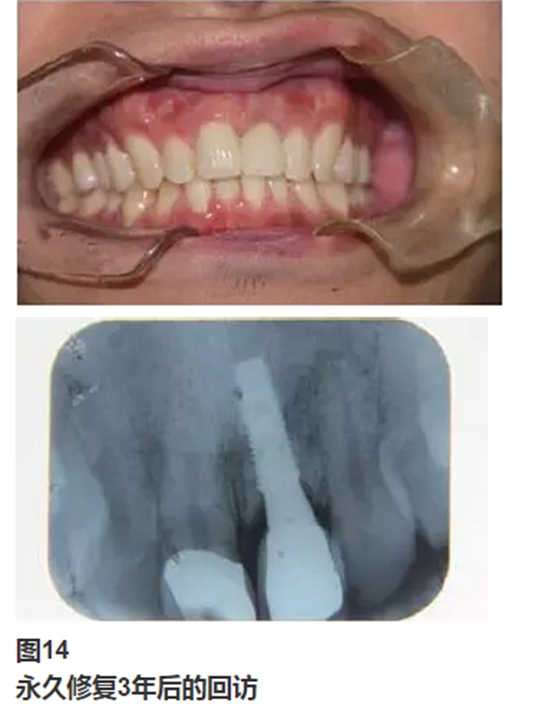

永久修復(fù)后3年進(jìn)行回訪,種植體骨結(jié)合穩(wěn)定,美學(xué)效果良好。